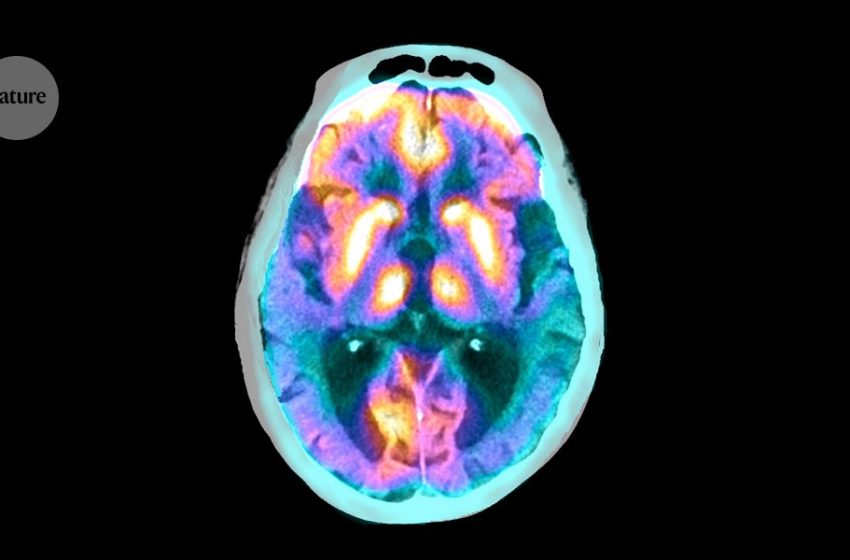

These brain cells clear proteins that contribute to Alzheimer’s

Credit: Zephyr/Science Photo Library

A group of specialized cells play a crucial part in clearing toxic proteins from inside the brain1. But in people with Alzheimer’s disease, these cells malfunction, leading to the build up of tau proteins — a hallmark of the disease.